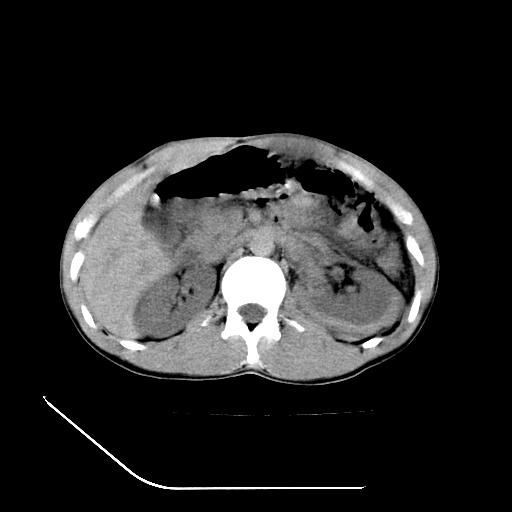

m-25y 高空堕落 12 月5号

12月7号病人尿量200ml/24h 急查双肾ct

左肾挫裂伤并肾周血肿;

肝肾间隙可见液区,建议手术探查;

左肾挫裂伤并肾周血肿

支持 : 左肾挫裂伤并肾周血肿

支持:1、左肾挫裂伤并肾周血肿;

2、少量腹水;

3、左肾旋转不良;

4、反射性肠淤张。

除了1:左肾挫裂伤并肾周血肿;

2:少量腹水

第二次ct检查后:临床医生腹水穿刺后考虑肠系膜动脉破裂,后实行剖腹探查:于空肠距离十二指肠90cm处发现肠管破裂,破裂口较小;修补后关腹。